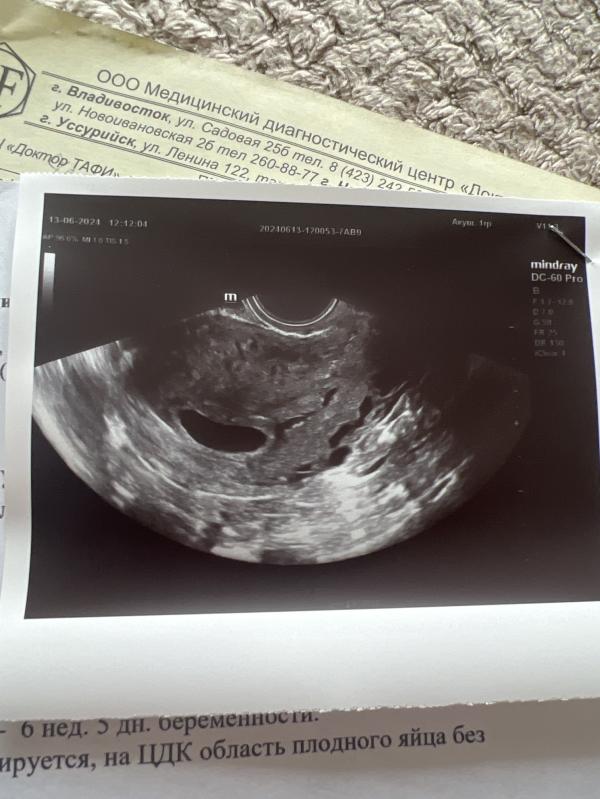

Только в этот раз пустое плодное яйцо, все соответствует сроку, вот только эмбриона нет и сердца у него тоже нет…

У меня до этого была замершая по причине генетической поломки, возможно это такой же случай. 3 недели ждать точно не смогу тк это очень долго и если действительно замерла вновь, то это чистка, а я еще раз это не вынесу- это ужасно. Но врач отложила аборт до 19 числа, к тому времени уже 8 недель будет . Вообще анэмбрионию диагностируют, когда ПЯ пустое и размерами 2,5 см. У меня уже было 2,41 вчера. Поэтому подождем до 19… я сейчас в смешанных чувствах, вроде смирилась, но вроде и хочется верить в лучшее. Спасибо за поддержку 🫂